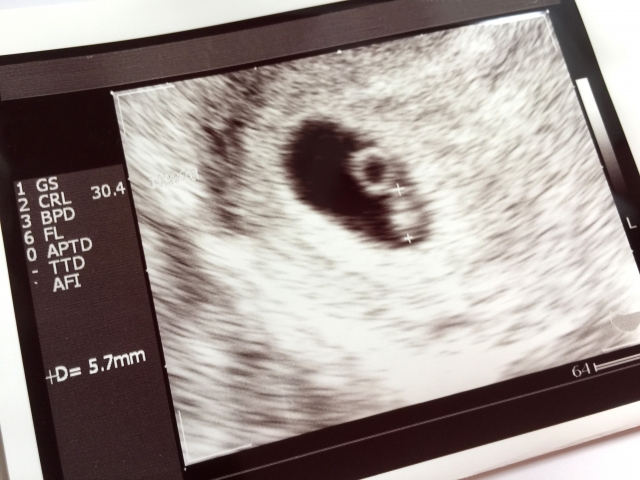

というのも、妊娠反応で子宮は膨らみ始めていても、エコーにはまだ何も確認できないということが多く、

せっかく時間もお金もかけて病院へ行っても、その労力は無駄足になってしまう事が多いからです。

病院で受診して、胎嚢や胎芽、心拍が確認できるまで通院しなければなりませんし、期待していた気持ちが一気に落ち込みになってしまうかもしれません。